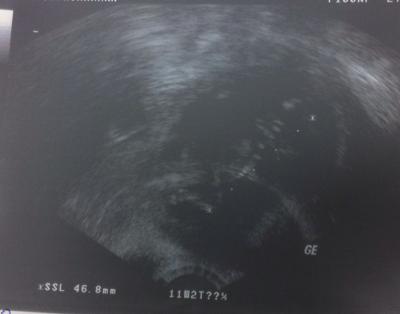

Hallo ihr lieben, ich hatte heute einen Termin beim FA. Dem Baby geht's gut, das Herz schlägt. Es ist ca. 4,7cm groß und hat sich viel bewegt. Ich war total fasziniert. Bei meiner ersten Schwangerschaft habe ich das so nie gesehen. Es hat sich richtig doll bewegt, sich sogar abgestoßen mit den Beinchen. Echt Wahnsinn, ich war total gerührt. Sogar das Gesicht konnte die Ärztin seitlich gut darstellen. Leider ist das Bild nicht so toll. Ich muss nun zu meinem Hausarzt. Der soll mir einen Langzeit-Blutdruckmesser geben. Habe 154/81 gehabt. Das letzt mal auch 151/84.